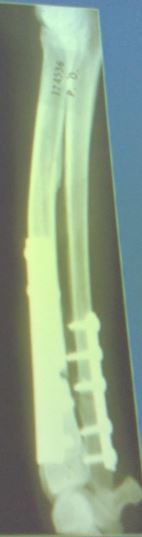

50

2 year old F mixed breed dog, 30kg. HBC 4 hours ago. Classify and assess fracture, and give repair options

Comminuted fracture of distal diaphysis of the femur Fx score: 6 Repair: ESF, Plate * IM pin + wire wont work* * Make sure you look for concurrent injuries (e.g. if hip luxated would also need Ehmers sling)*